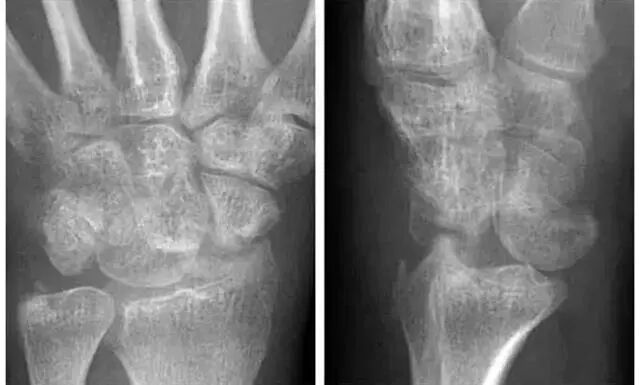

Case 分析1

1.月骨-三角骨间隙不平行,存在重叠。

2.钩状骨和月骨也存在重叠。

3.桡骨、月骨、舟骨近极和头状骨近极平行关系存在。

4.三角骨、钩骨、头状骨远极、大多角骨和舟骨远极平行关系也存在。

5.头状骨和舟骨骨折。

诊断:经舟骨、经头状骨月骨周围骨折-脱位。

Case 分析2

舟骨-大多角骨-小多角骨关节(STT关节)、第1腕掌关节(CMC1关节)严重骨关节病伴半脱位,掌骨弧线正常、平行关系存在。舟骨变长提示其向背侧倾斜。

侧位片示月骨也向背侧倾斜,近排腕骨作为一个整体移动,所以不存在脱位。

最后诊断:无脱位DISI(背屈不稳)伴STT关节骨关节病及半脱位。

侧位显示月骨向掌侧倾斜

Case 分析3

1.月骨-三角骨间隙平行关系缺失致掌骨弧线I and II中断。

2.月骨和舟骨平行,而与其他腕骨不平行。

3.舟骨缩短提示向掌侧倾斜。

4.月骨平行于舟骨,其三角形状提示为掌侧倾斜所致。

5.近排腕骨不是一个整体,因为弧线I中断。

诊断:掌屈不稳伴月骨-三角骨关节脱位